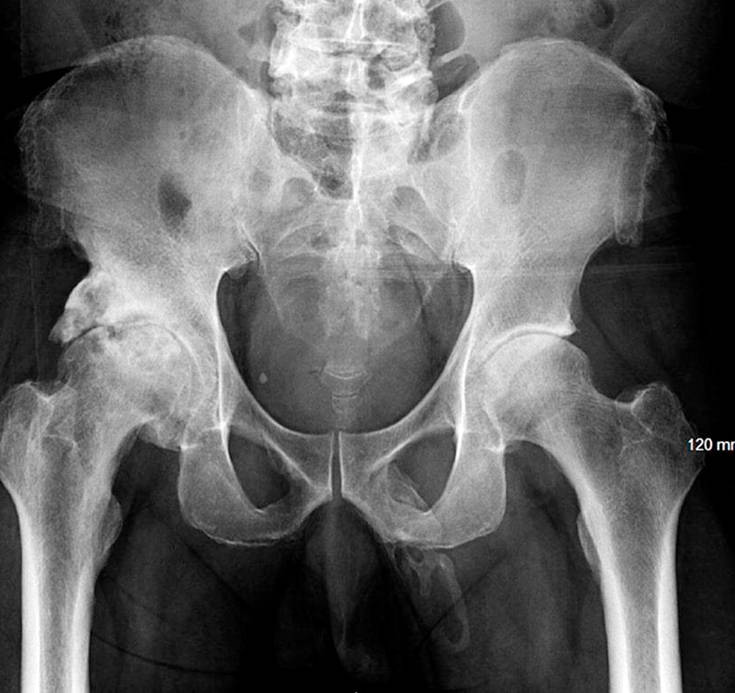

Οι γιατροί παρατήρησαν ωστόσο έκπληκτοι στην ακτινογραφία ότι οστεοκύτταρα σχηματίζονταν πάνω στον ανδρισμό του. Μοιράστηκαν μαζί του τα νέα, αλλά το σοκ ήταν προφανώς ανυπέρβλητο που ο άντρας έφυγε από το νοσοκομείο και δεν ξαναγύρισε ποτέ!

Έτσι περιγράφουν το περιστατικό στο άρθρο τους στο περιοδικό «Urology Case Reports», καθώς η ιστορία έμεινε εκεί. Αρκεί πάντως να πούμε ότι λιγότερα από 40 τέτοια περιστατικά έχουν καταγραφεί στα ιατρικά χρονικά και κάποιες φορές συνδέονται με νεφροπάθειες και καρκίνους.